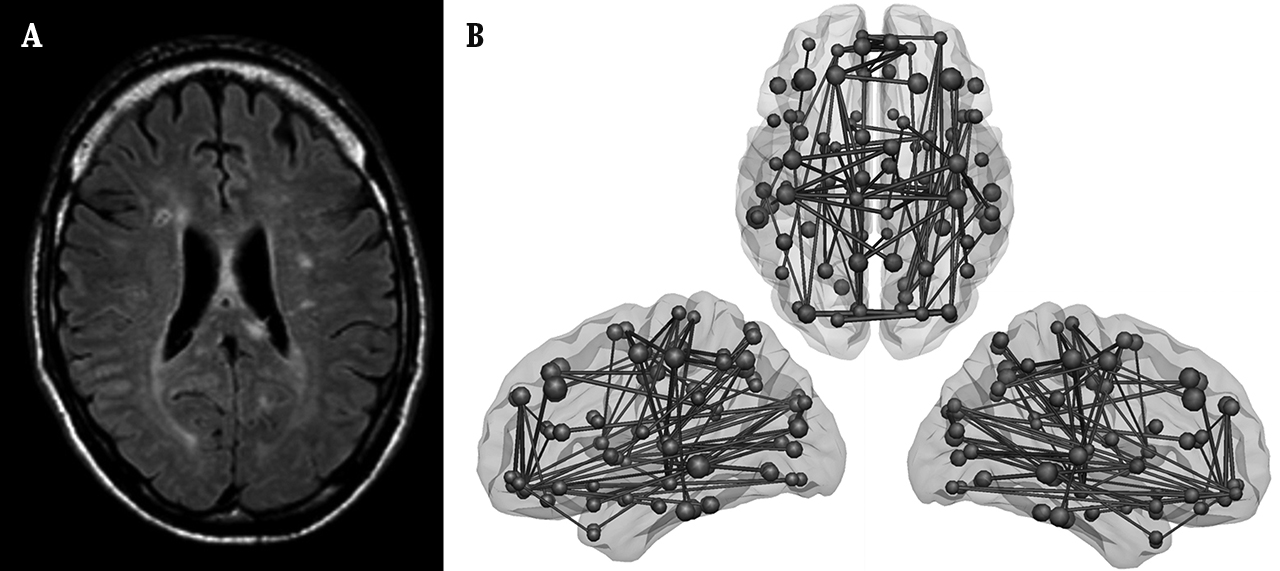

In een recent onderzoek hebben wij deze hypothese over de relatie tussen laesielocatie in het netwerk en cognitie onderzocht (Reijmer e.a., 2016). Van 135 patiënten van de geheugenpolikliniek met verschillende gradaties van wittestofpathologie hebben we het hersennetwerk in kaart gebracht. Het netwerk werd gereconstrueerd op basis van de DTI-scans en bestond uit verbindingen tussen zestig vooraf gedefinieerde hersengebieden (zoals in Figuur 1). Vervolgens hebben we de zogenaamde 'snelwegen' van het netwerk in kaart gebracht. Een verbinding werd aangemerkt als een snelweg als deze relatief vaak gebruikt wordt om informatie over te brengen tussen hersengebieden. Dit wordt aangegeven door een hoge 'centraliteit' binnen het netwerk. Microstructurele schade (lagere FA) aan de centrale verbindingen van het hersennetwerk zorgde voor een relatief grote verstoring van het netwerk als geheel: het netwerk werd minder efficiënt. Dit leek zich ook te vertalen naar problemen met het cognitief functioneren: microstructurele schade aan de centrale verbindingen van deze patiënten verklaarde meer variatie in het executief functioneren dan microstructurele schade aan de overige verbindingen. Deze resultaten zijn in lijn met de principes van de netwerktheorie: als een kritiek onderdeel van het netwerk is aangedaan, heeft dat relatief grote gevolgen voor het functioneren van het netwerk als geheel.

Figuur 1 Analyse van het hersennetwerk op basis van DTI-gewogen MRI-beelden. A) De wittestofverbindingen van het netwerk worden gereconstrueerd met behulp van tractografie. B) De punten van het netwerk worden bepaald door de grijze stof op te delen in een aantal gebieden. Hier wordt vaak een standaardbreinatlas voor gebruikt. C) Op basis van A en B kan worden bepaald welke hersengebieden (punten) met elkaar in verbinding staan. D) Met behulp van de netwerktheorie kunnen verschillende karakteristieken van het netwerk als een getal worden uitgedrukt. Een voorbeeld is de kortste afstand tussen elk paar punten of het aantal connecties dat samenkomt in een punt. De kwaliteit van de connecties wordt meegewogen in de berekeningen (in de figuur aangegeven met verschillende lijndiktes).